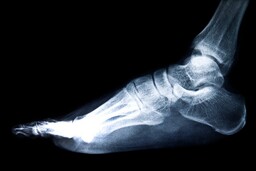

Muscles are connected to bones with tendons. For example, the upper part of the calf muscle is connected to the tibia by a tendon, whereas the lower part of the same muscle is connected to the heel via the Achilles tendon.